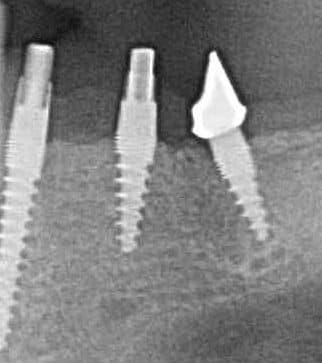

Oui,c´est un Prep cap zircone , que je cémente juste après l´implantation immédiate pour mieux former la gencive. Les implants monoblocs ont étés implantés entre 40 et 60 Ncm . Les photos 6 et 8 on voit les prep cap juste après l´implantation immédiate ce sont des sortes de "couronnes" pré fabriquées.

Oui , tu as raison pour la 45, en fait quand j´ai enlevé la 45 j´ai choisi l´axe comme ca ( dans l´os dur et en bon santé) parce que c´etait ici que je pouvais avoir la stabilité ( pour cet implant à 50 Ncm.

Radios 1,2,3 photo 1= jour de la pose de l'implant.

radio 4 photo 2 et 3= 8 semaines post pose de l'implant, ceramiques scéllées.

Radio 6, photo 4 et 5 controle à 24 mois.

Deux ans plus tard, la gencive a recouvert la zircone et on observe à la radio un gain osseux au niveau des micros spires.